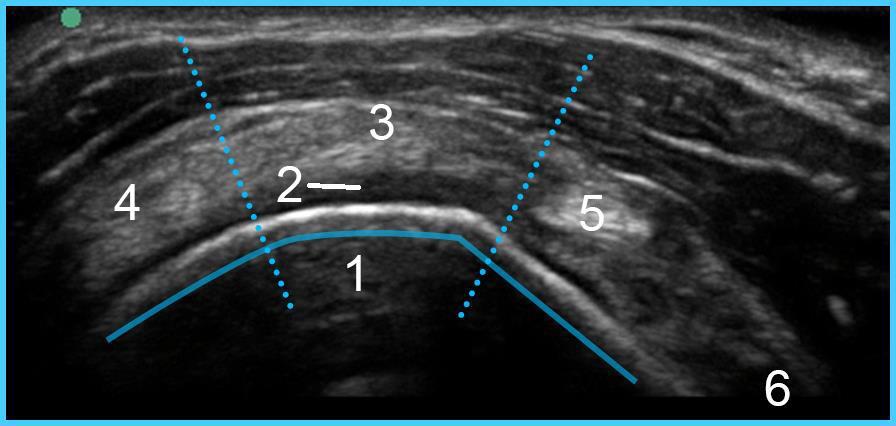

1. Tête humérale

2. Cartilage hyalin articulaire

3. Tendon supra-épineux (Avant insertion)

4. Tendon infra-épineux (Avant insertion)

5. Tendon du biceps (dans l'intervalle de la coiffe des rotateurs inter articulaires)

6. Tendon sous-scapulaire